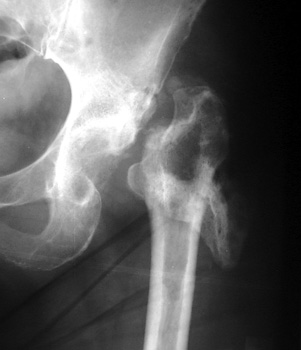

INFECTION—Markedly widened interfaces about acetabular and femoral components

INFECTION Progressive interface widening about acetabular component